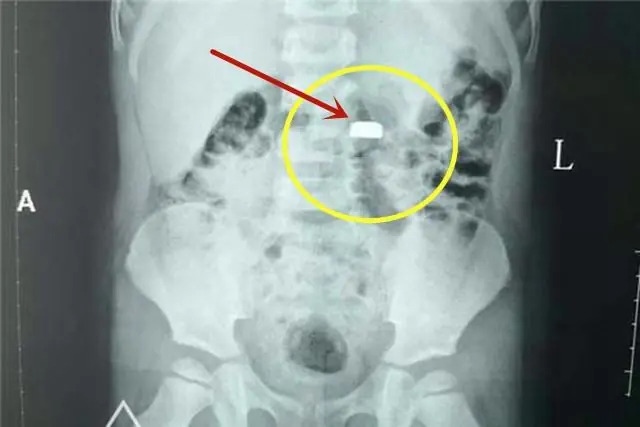

Viên pin cúc áo mà bé trai 3 tuổi của chị Linlin nuốt phải gây nguy hiểm dù tới bệnh viện ngay sau đó

Mắt đã ngấn lệ nhưng chị Linlin không tranh cãi với họ. Chị ôm con ra khỏi nhà, bắt taxi đến thẳng bệnh viện. Sau khi đứa bé được cấp cứu thành công, lấy được viên pin cúc áo ra ngoài, chị mới ngồi bệt xuống hành lang bệnh viện mà khóc nức nở. Một vị bác sĩ tới an ủi chị và nói: "Chị xử lý như vậy là rất nhanh trí, rất giỏi. Chị chính là người cứu được thực quản của cháu bé".

Quan trọng nhất, cần nhớ, dù dùng mật ong hay phương pháp sơ cứu nào cũng phải đưa trẻ đi cấp cứu càng sớm càng tốt ngay sau đó. Thông báo rõ hoặc mang theo loại pin trẻ nuốt phải. Bác sĩ sẽ sắp xếp chụp X-quang, CT và ưu tiên phương pháp nội soi để gắp pin ra sớm nhất có thể, ngăn chặn hóa chất rò rỉ phá hủy nội tạng.